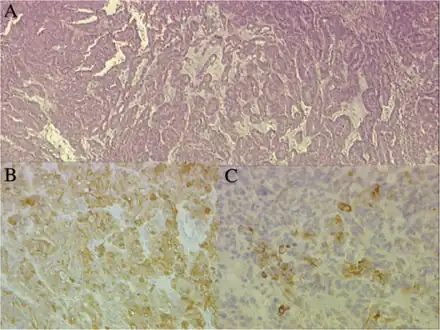

a)Papillary and tubular patterns represent the distinctive appearance of medulloepithelioma b)positivity of the neoplastic cells for S100 protein c) PanCytokeratin

Neuronal differentiation, ranging from neuroblasts to ganglion cells, is seen in some medulloepitheliomas.

Histologically, medulloepithelioma resemble a primitive neural tube and with neuronal, glial and mesenchymal elements.[8][9] Flexner-Wintersteiner rosettes may also be observed.[10]

Immunohistochemically, neural tube-like structures are vimentin positive in the majority of medulloepitheliomas.[11] Poorly differentiated medulloepitheliomas are vimentin negative.